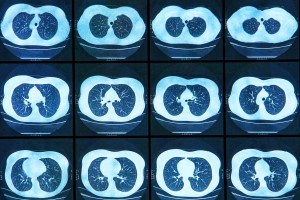

Cystic fibrosis (CF) affects multiple organs and can cause gastrointestinal disease, liver disease, pancreatic disease, reproductive disorders and diabetes. CF can also lead to lung disease, the most common cause of lower life expectancy related to CF.